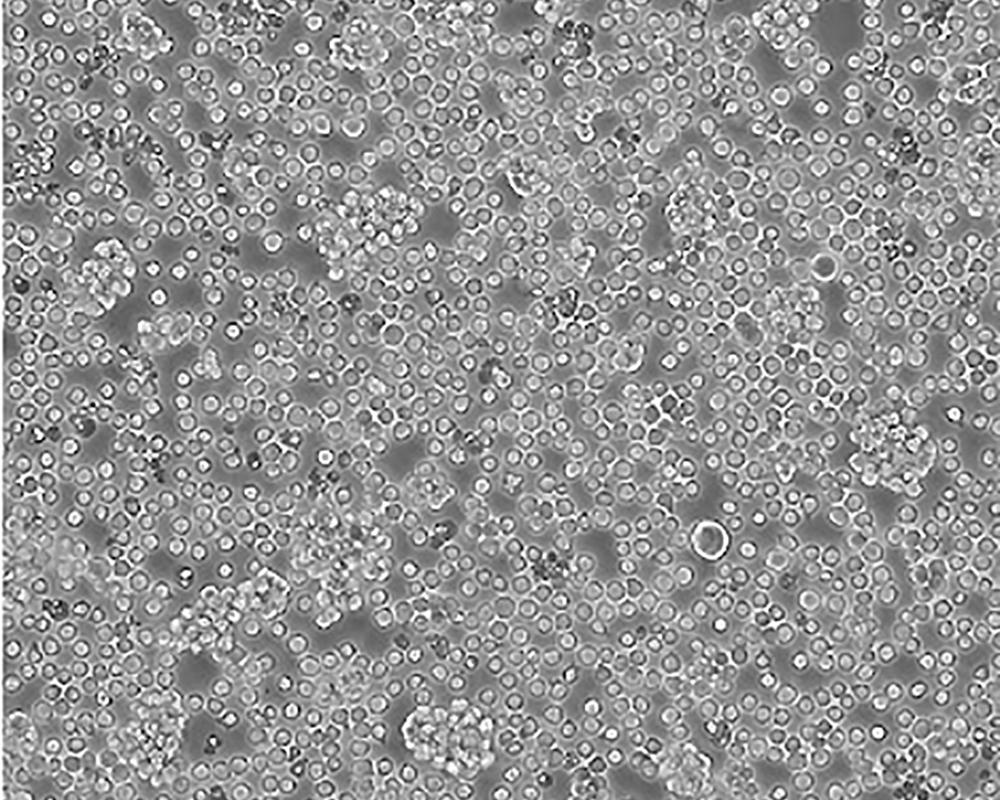

Jurkat, Clone E6-1 [Jurkat E6-1]

人T淋巴細胞白血病細胞

急性T淋巴細胞白血病;男性

suspension

lymphoblast

該細胞是Jurkat-FHCRC細胞株(Jurkat細胞株的衍生)的一個克隆。Jurkat細胞株來源于一個14歲男孩的外周血。經佛波酯和外源凝集素或抗T3單克隆抗體誘導后可產生大量IL-2(IL-2的產生需兩種類型的誘導劑);表達T細胞受體、CD3